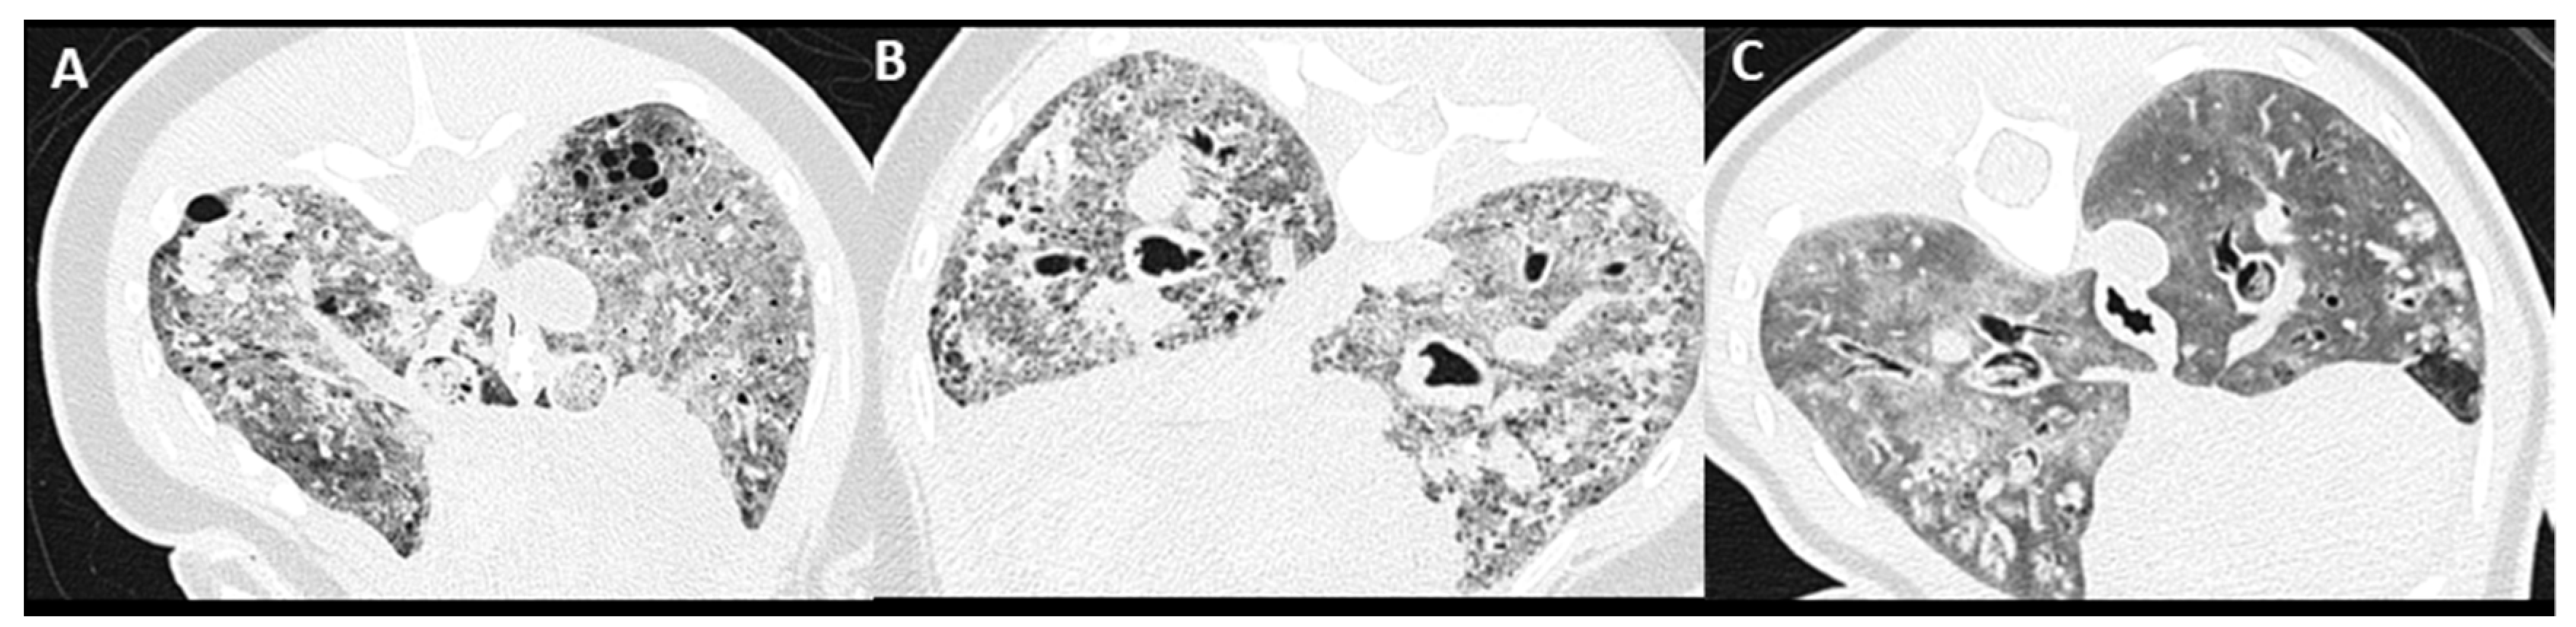

3.4. Pulmonary Parenchymal Attenuation Changes